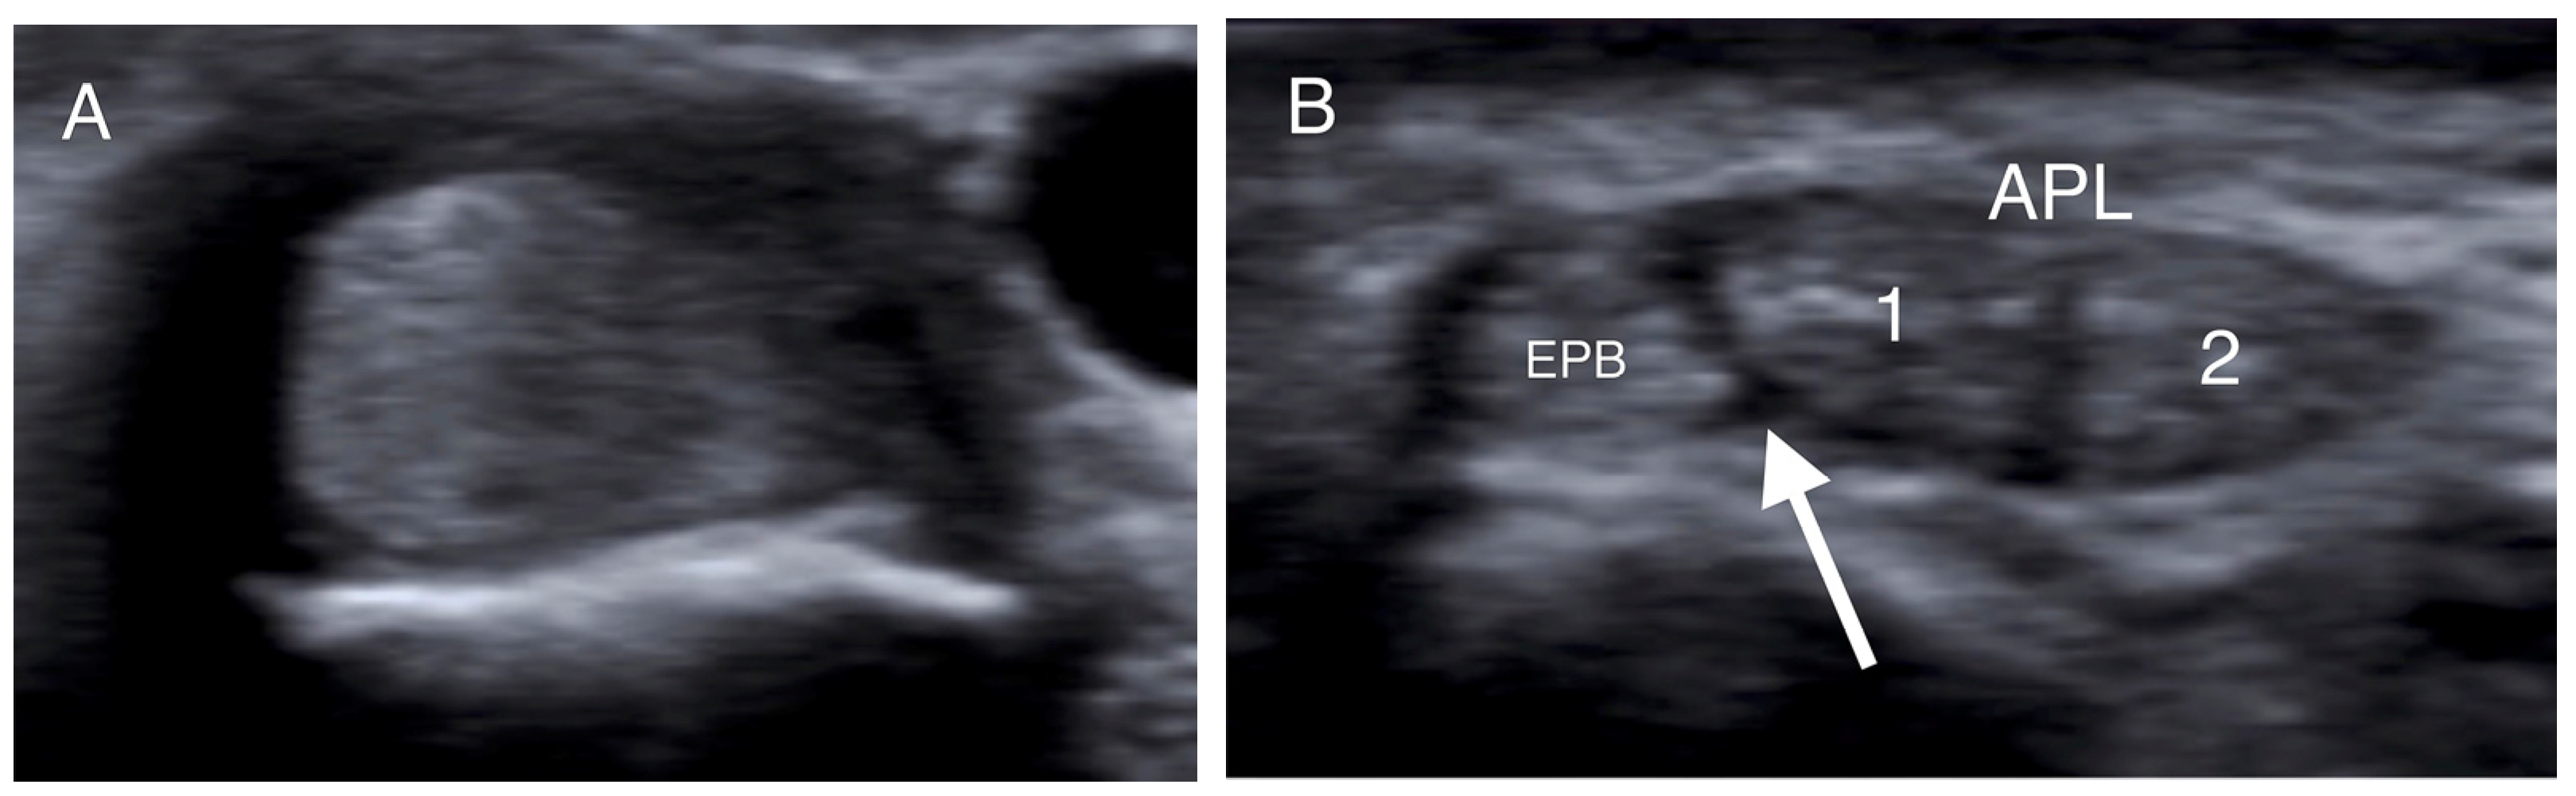

- Choi, S.J.; Ahn, J.H.; Lee, Y.J.; Ryu, D.S.; Lee, J.H.; Jung, S.M.; Park, M.S.; Lee, K.W. De Quervain Disease: US Identification of Anatomic Variations in the First Extensor Compartment with an Emphasis on Subcompartmentalization. Radiology 2011, 260, 480–486. [Google Scholar] [CrossRef]

- Kwon, B.C.; Choi, S.J.; Koh, S.H.; Shin, D.J.; Baek, G.H. Sonographic Identification of the Intracompartmental Septum in de Quervain’s Disease. Clin. Orthop. Relat. Res. 2010, 468, 2129–2134. [Google Scholar] [CrossRef]

- Abi-Rafeh, J.; Mojtahed Jaberi, M.; Kazan, R.; Alabdulkarim, A.; Boily, M.; Thibaudeau, S. Utility of Ultrasonography and Significance of Surgical Anatomy in the Management of de Quervain Disease: A Systematic Review and Meta-Analysis. Plast. Reconstr. Surg. 2022, 149, 420–434. [Google Scholar] [CrossRef] [PubMed]

| Double groove | 12 (24%) |